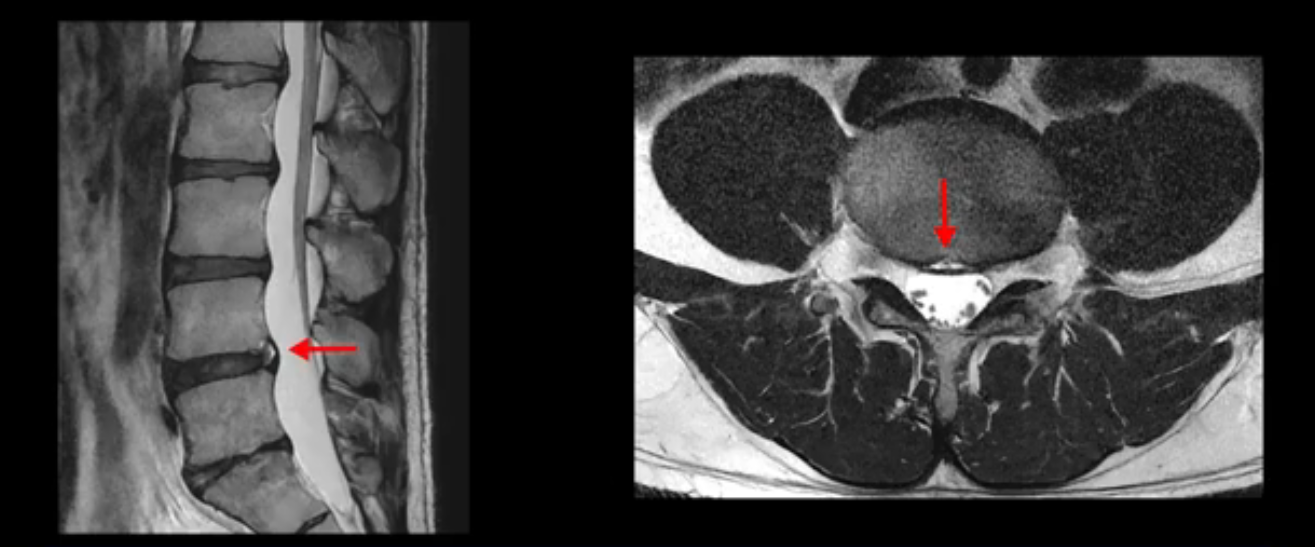

4번 5번은 가운데로 섬유륜이 찢어져서 디스크가 살짝 밀려나와 있지만 역시나 최근에 찢어지고 밀려나온 걸로 판단되지 않고 오래 전에 찢어진 흔적으로 보입니다.

왜 최근에 찢어진 급성이 아니고 오래된 거라고 하는지 이 부분도 뒤에 한꺼번에 설명 드리겠습니다.

5번 1번 역시 가운데로 디스크 조금 밀려 나와있지만 신경 공간 넓이는 아주 넓어서 신경 눌림 있을 거라고 예상이 안됩니다.

앞서 1번 2번, 4번 5번, 5번 1번의 디스크가 찢어지고 조금 밀려 나온 게 최근에 찢어진 게 아니고 오래된 걸로 보인다고 말씀 드렸죠. 왜 그럴까요? 만약 급성으로 찢어진 것이라면 아주 심한 디스크성 통증이 있겠죠. 기침이나 재채기를 하면 심하게 아프고 허리를 조금만 구부리거나 비틀면 아주 날카로운 통증들이 생길 겁니다. 그런데 이분은 이런 증상이 전혀 아닙니다. 또 디스크의 밀려나온 정도도 전혀 심하지 않기 때문에 이분이 가지고 계신 양쪽 다리 저림, 특히 이분은 누워있을 때도 양쪽 발이 발가락까지 쑤신다고 하는데 이정도 디스크 때문에 그런 증상은 생길 수가 없는 겁니다. 이처럼 이분의 가벼운 디스크 탈출은 이미 오래 전에 진행되었고 섬유륜 자체는 이미 아문 상태인데도 디스크내장증을 진단받은 환자들 중에는 본인이 섬유륜 파열 환자라고 끝까지 믿는 분들이 많습니다. 다시 말하지만 디스크내장증이라는 진단을 받은 환자들을 보면 거의 전부 다 섬유륜 파열 증상이 아닙니다. 증상이 완전히 다릅니다. 진단이 애초에 잘못되면 어떤 치료를 받아도 좋아질 수 없습니다.

이분은 어떤 한 병원에서 디스크 내장증 얘기를 들으셨는데요. 여기 보시는 것처럼 4번 5번의 하얀 HIZ(High Intensity Zone)을 보고 디스크 내장증의 근거로 얘기하는 병원들이 있는데,

이 HIZ는 섬유륜이 찢어졌다가 이미 아문 뒤에도 얼마든지 보일 수 있는 흔적일 가능성이 있어서 재채기를 하면 아픈지, 허리를 구부릴 때 날카로운 통증이 생기는가 등의 증상으로 구별해야 하는데 MRI만 보고 HIZ가 보이면 그게 마치 통증의 원인인 것처럼 얘기하는 의사들이 있습니다. 이분 MRI를 자세히 보고 증상을 정말 자세히 들어본 의사가 있었더라면 다른 환자분들처럼 증상과 MRI가 일치하지 않는다는 얘기를 들을 수 있었을 텐데 이분은 그런 얘기는 듣지 못했습니다.